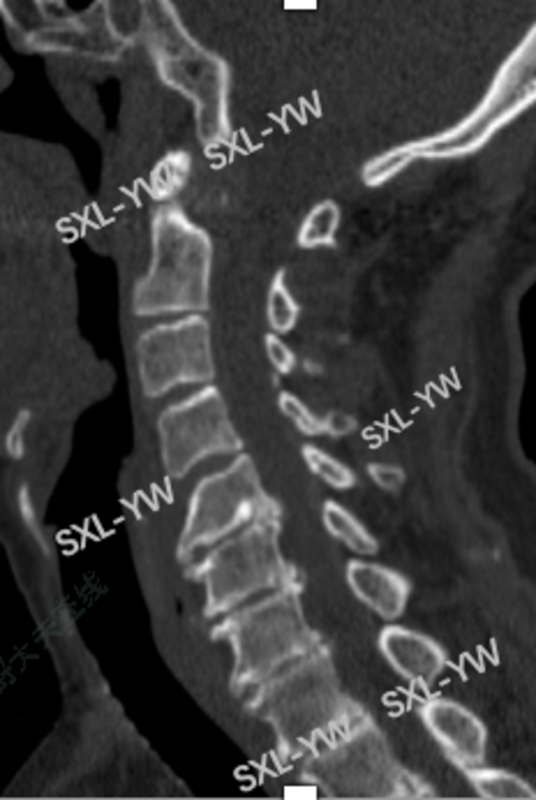

术前CT提示:严重颈椎退变,椎体前后缘大量骨赘增生,椎间隙高度完全塌陷并骨性融合。